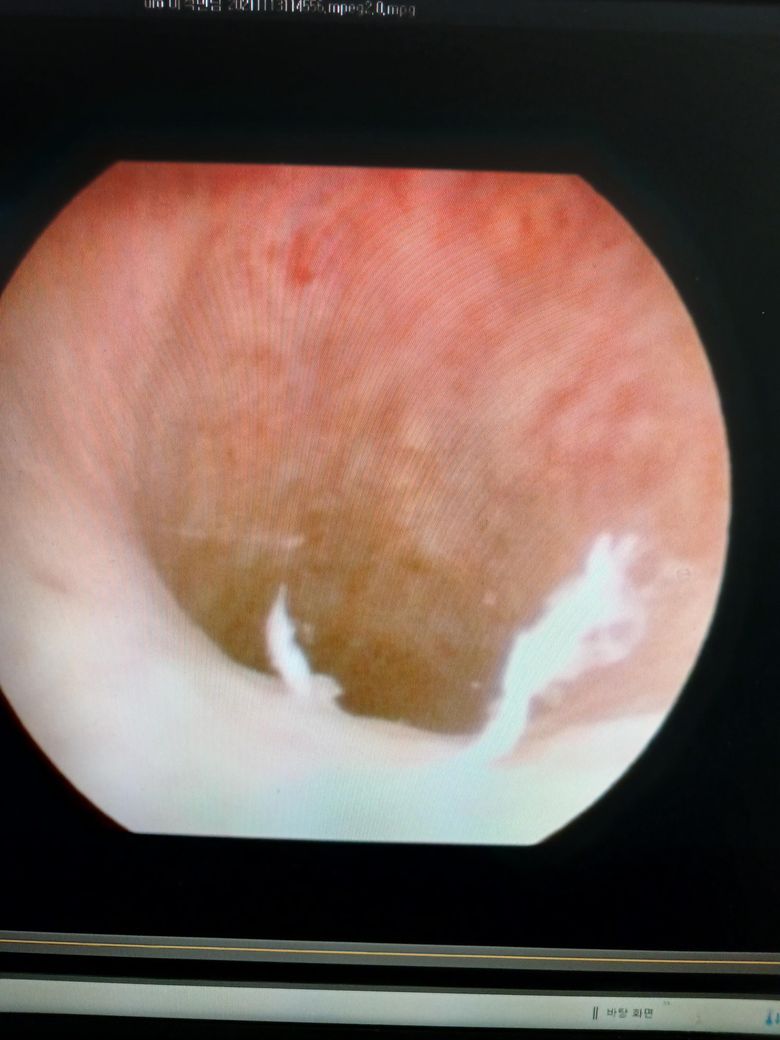

• 2번 째 사진

점막이 탈락되면서 소변으로 저절로 빠져 나갑니다.

내시경 사진으로 보아 더 크게 느껴지는 것이지, 실제 크기는 무척이나 작아 육안으로 자세히 봐야 보일 정도입니다.

크게 걱정하지 않으셔도 될 것으로 판단됩니다.